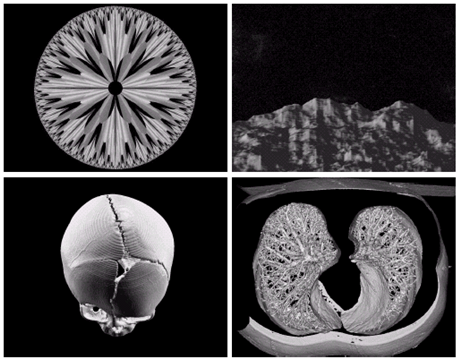

Fields of Digital Image Processing

• Image의 energy source에 따라 digital image processing의 범위를 이해

- Gamma선, 자외선, 가시광선, 적외선, radio wave

- 초음파, 전자현미경, computer-generated image

Image

Gamma ray image

• 감마선의 투과성을 이용

• 주요 응용분야: 핵의학, 천문관측

a) 환자에게 감마선을 방사하는 방사선 동위원소를 주사, 감마 검출기로써 영상을 획득 - 병소의 위치 파악에 유용 b) PET(positron emission tomography) image c) 백조자리 15,000년전의 가스성운의 감마선 영상 d) 핵반응 밸브로부터 나오는 감마선(밝은 부분)

X-ray image

• X선의 투과성을 이용

Ultraviolet image

• 주요 응용분야: 석판인쇄, 산업용 검사, 형광 현미경, 레이저, 생물학 영상, 천문 관측 등

a) 보통옥수수 b) 깜부기병에 걸린 옥수수 c) 백조자리 성운

Visual band and infrared image

• 적외선 영상은 가시광선 영상과 함께 사용되는 경우가 많다

a) 항암제 Taxol b) 콜레스테롤 c) 마이크로프로세서

Multispectral(가시광선과 적외선) image of Hurricane Andrew

Infrared image

남북 아메리카의 적외선 위성사진 (인구밀도를 보여줌)

• 전자현미경: SEM(scanning electron microscope)

• 전자빔을 쏘아 각 위치에서 빔과 샘플과의 상호작용을 기록

텅스텐필라멘트의 250x SEM영상, 손상된 IC의 250x SEM영상